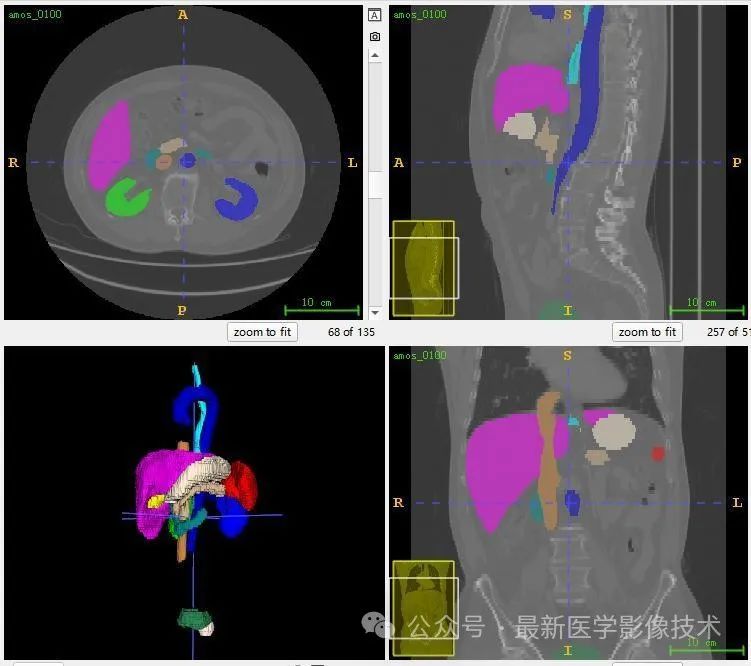

13、测试集分割结果